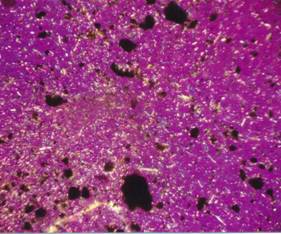

Drobné jehličkovité krystaly močanu

sodného v polarizačním mikroskopu, zrnkový preparát,

zvětšeno 360x